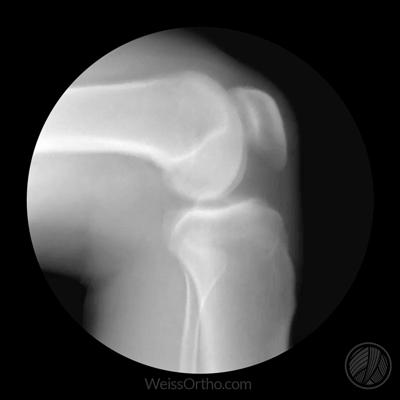

髌骨是我们人体最大的一块籽骨,针对我们的膝关节有非常重要的作用,如果将髌骨切除,我们膝关节伸直的力量将会降落30%左右,这个作用有点类似于杠杆的支点。

在膝关节做屈膝运动的时候,角度达到20度左右,髌骨开始与后方的股骨接触,两者之间开始有压力存在,随着屈膝角度的加大,髌骨与股骨之间的压力也会越来越大。如果膝关节完全伸直,髌骨并不会受到过度的压力,明白以上这两点非常的重要。

一般情况下,髌骨骨折做完手术以后,我们会建议患者适当的进行膝关节的屈伸运动,但是我们会限制角度,一般是控制在0度到30度左右之间,这样的话,髌骨并不会承受大的压力,不会影响骨折的部分,而且也不会造成关节的粘连。但如果患者关节的伤情比较重,关节不能进行正常的屈伸或者是康复介入的比较晚,那么就有可能导致出现膝关节的粘连,患者可能会出现明显的屈、伸膝关节范围受限,而且在进行屈伸关节的时候会有明显的疼痛感。另外有的患者害怕在进行康复锻炼的时候,加大髌骨的压力,导致骨折再次断裂,所以不敢活动,也是导致很多患者出现膝关节粘连的原因。